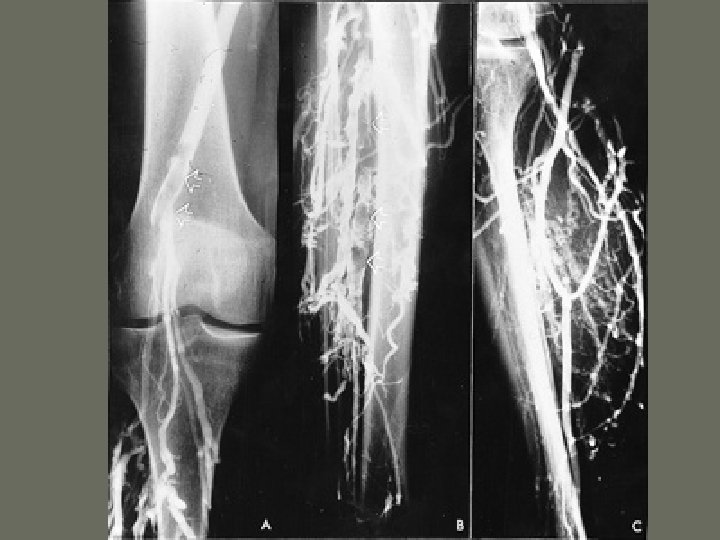

General Angiography Procedures 5. Peripheral Angiography • radiographic study of the vessels of the upper or lower limbs following the injection of contrast medium • Abdominal Aortography with _______

Interventional Procedures 3. Percutaneous Transluminal Angioplasty – PTA • purpose is to _____ a stenotic vessel or to cannulize short arterial occlusions • compresses the _______ material against the vessel wall • arterial pressures are recorded prior to procedure

Interventional Procedures • Uses a ______ catheter – catheter placed over the stenosis and inflated with contrast medium